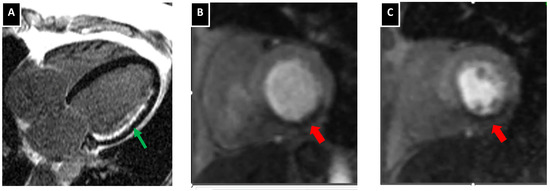

| LGE cMRI | − | − | Viability assessment |